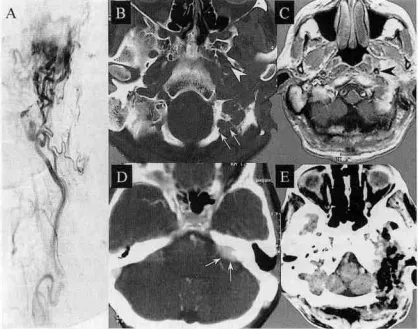

该患者26年前在另一家机构通过经乳突经迷路通路进行了手术,术中牺牲面听神经。一开始手术失败后6年再次尝试面部神经移植术。入院前几个月,患者出现进行性左侧三叉神经痛,很可能是颞下窝肿瘤压迫五神经二和三分支所致。此外,患者出现频繁的反应性高血压和植物神经功能失调。术前MRI和CT扫描(图2)显示一个从颈静脉孔向前延伸至颈动脉的大肿瘤,并被肿瘤的岩骨部分包裹。骨窗CT扫描显示肿瘤侵犯枕髁。出现一过性吞咽困难,除此之外,患者的术后病程平安无事。三叉神经痛和反应性高血压完全消失。

图示:A,术前左颈内动脉造影显示高度血管化的肿瘤。B,术前CT扫描上的箭头显示肿瘤侵蚀区域位于枕骨髁下的枕骨大孔内侧缘,而箭头指向颈内动脉。C,术前MR的箭头显示肿瘤向前延伸并包裹颈内动脉。D,术前CT增强扫描显示肿瘤经内耳道向颅内延伸。E,肿瘤切除后经联合经髁经岩入路行CT扫描,显示全切及受肿瘤侵犯的骨质被全切除,残腔使用腹部脂肪组织填塞闭塞。